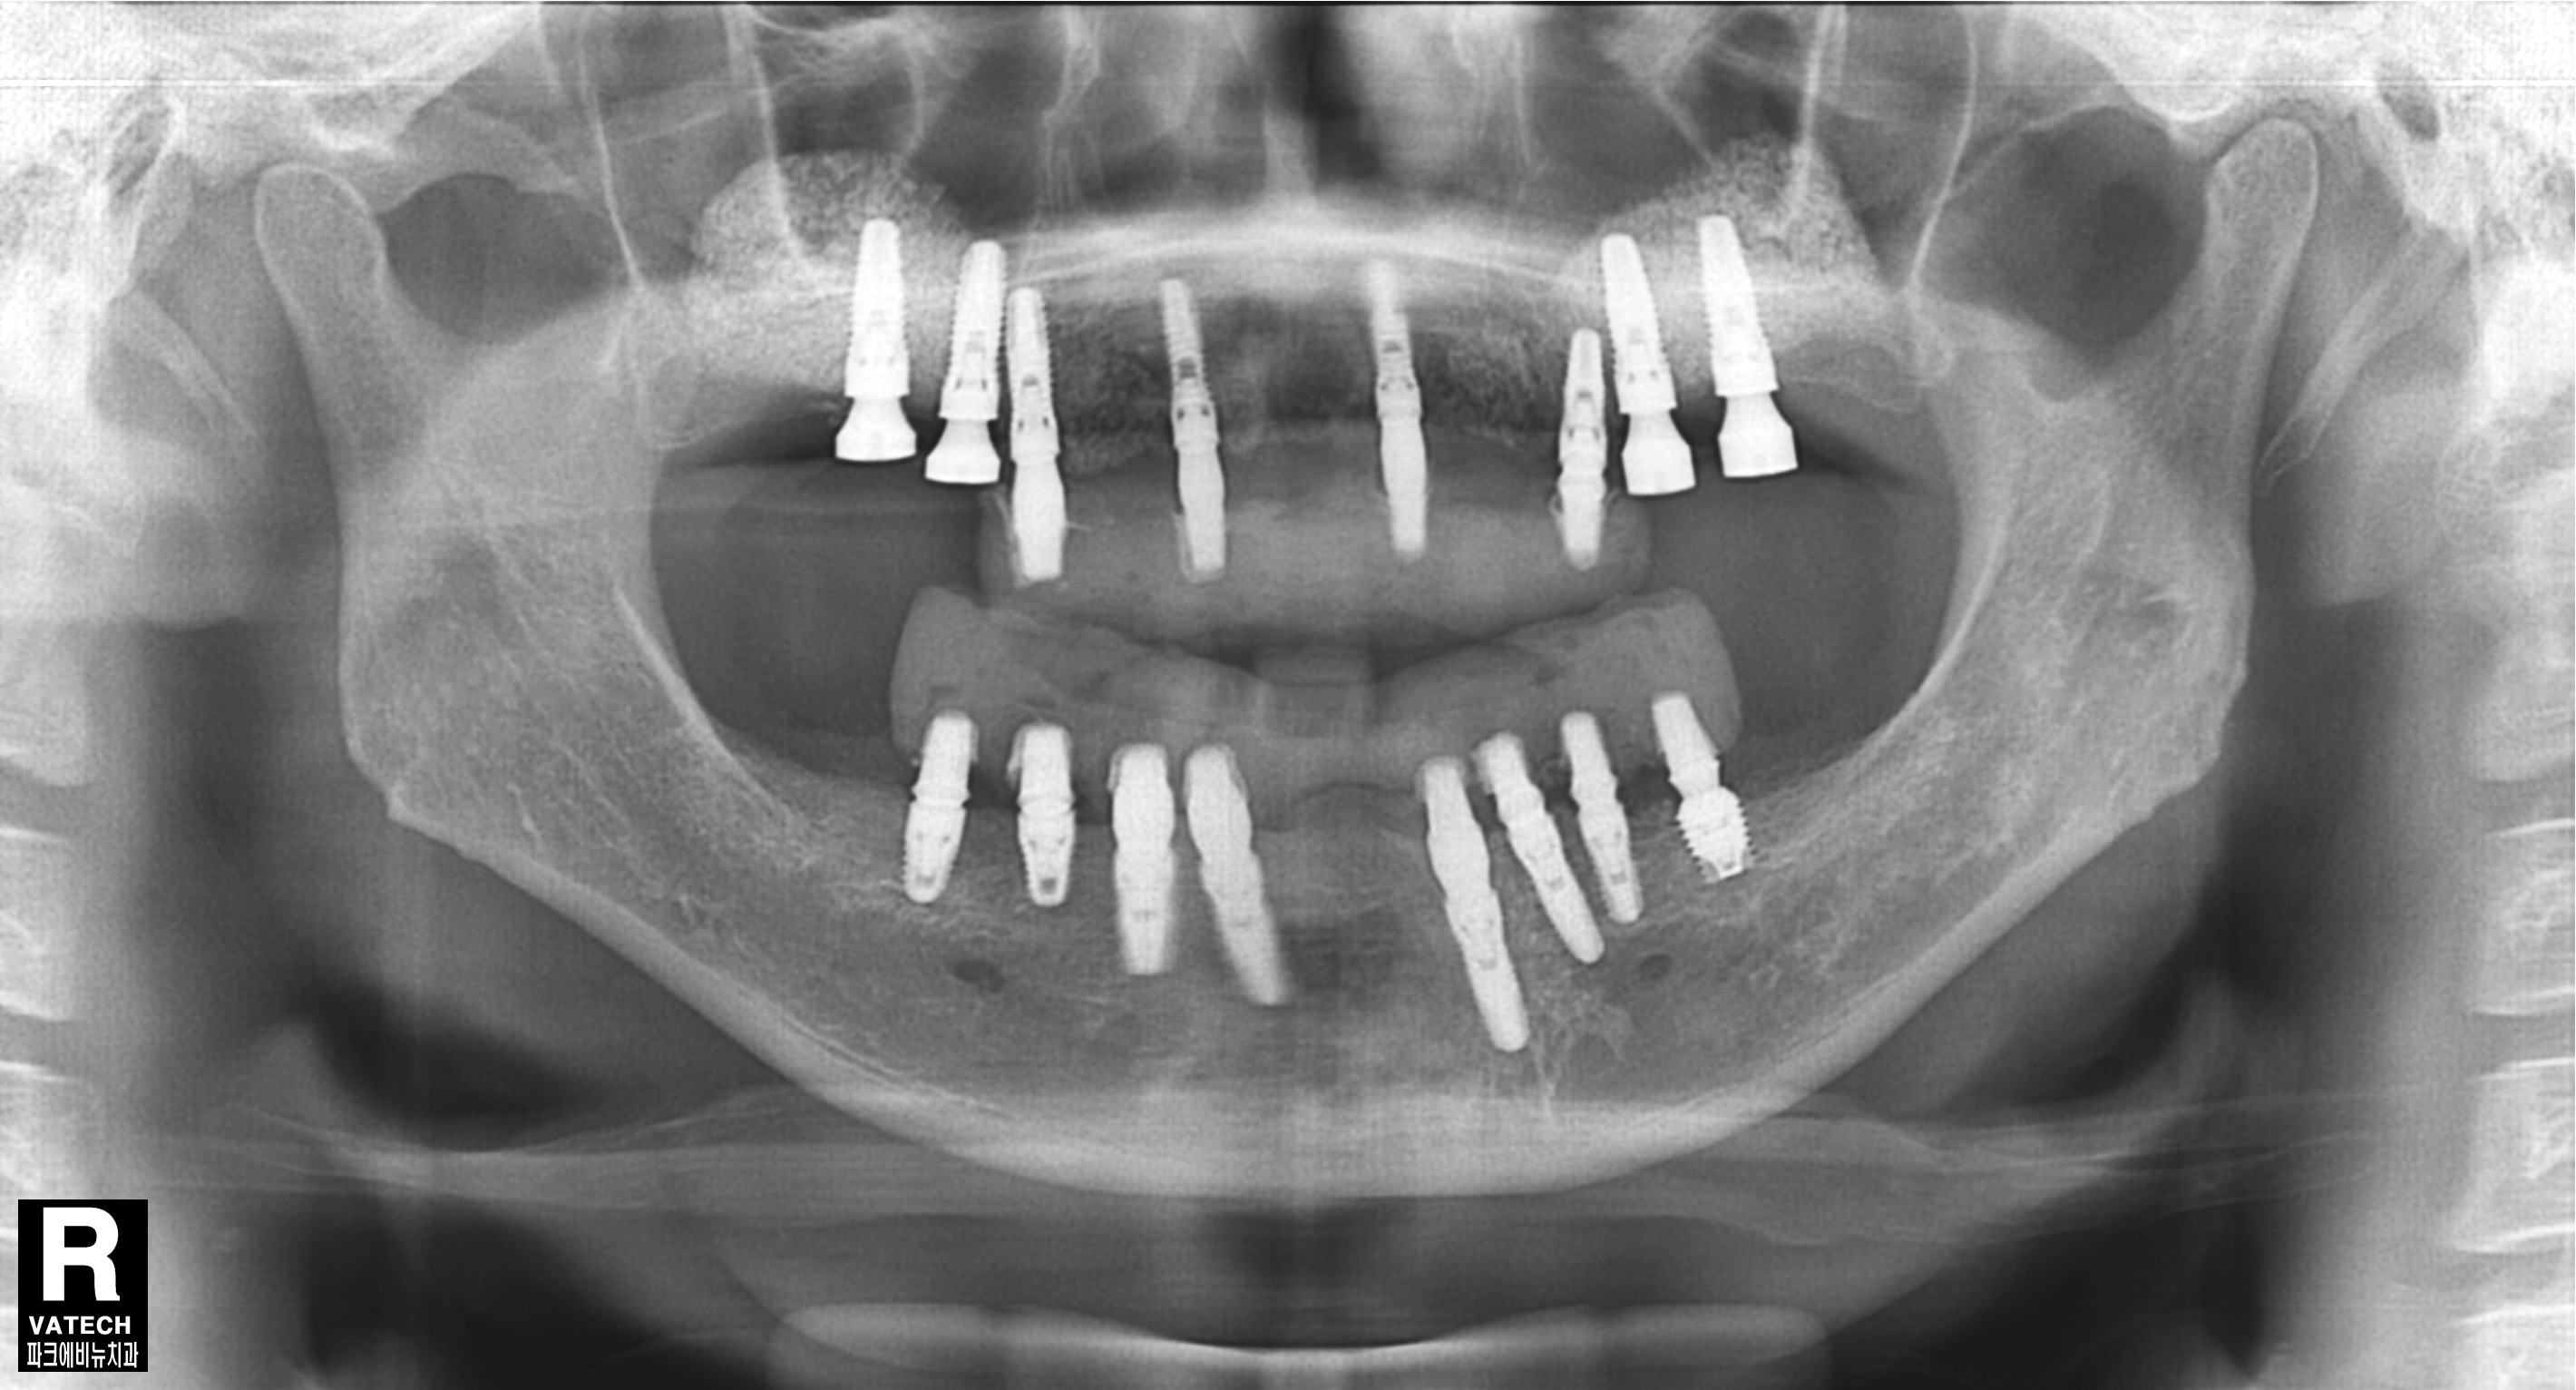

파노라마 방사선 사진도 살펴보면 치아를 잡는 치조골이 치아 뿌리 끝까지 많이 녹았음 확인할 수 있었습니다.

치료 중 찍은 방사선 사진입니다.

치료 필요에 따라 뼈이식도 진행하였습니다.